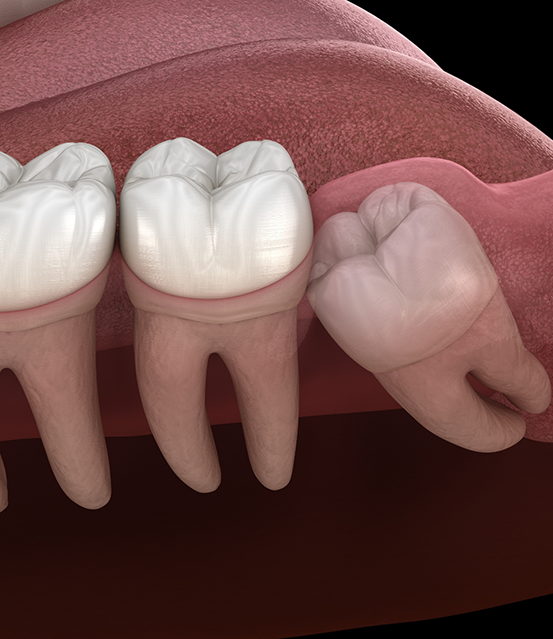

Wisdom teeth, or third molars, can erupt in your late teens and early twenties. Sometimes, these molars do not have enough room to come in properly. It might lead to crowding and infection. Here are some common reasons to get it removed:

- A trapped or partially erupted wisdom tooth can push against your neighboring teeth. You might experience swelling, chronic discomfort, and cysts if left untreated.

- The third molars can damage or shift your second molars. Lack of enough space might lead to root damage and alignment problems.

Our office offers you both simple and complex extractions. We also offer services to remove a fully bony impacted tooth that has not emerged from the gums.